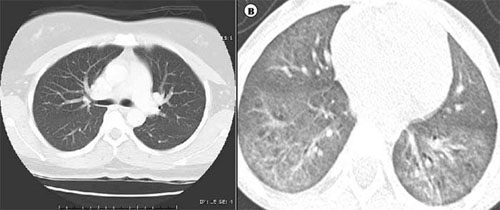

왼쪽 사진은 정상 성인의 흉부전산화단층촬영(CT) 소견으로, 검게 보이는 곳들이 폐실질(폐포와 공기가 있는 곳)이다. 오른쪽 사진은 가습기 살균제로 손상 받은 소아의 흉부전산산화단층촬영(CT) 소견으로, 검게 보여야 할 곳이 염증과 폐섬유화로 인해 하얗게 보인다. 유리를 갈아 놓은 것 같다고 해서 ‘간유리음영’이라고도 부른다.